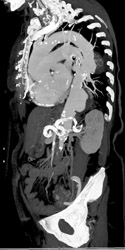

Aortic Aneurysm